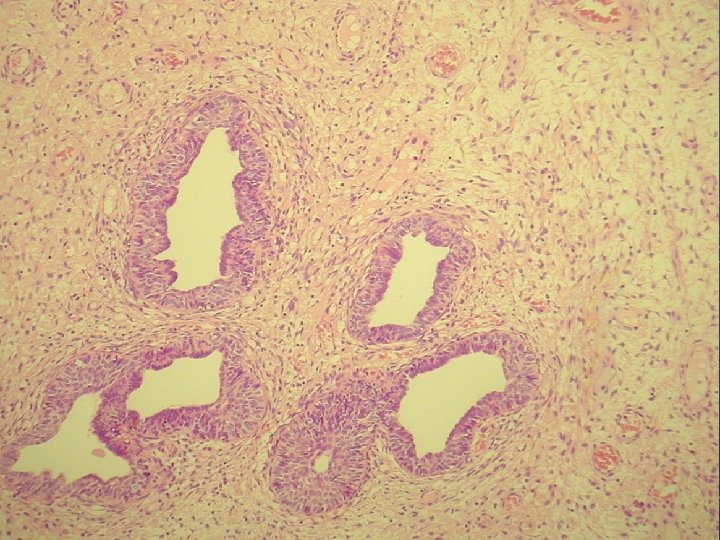

prolaps tuby asociovaný s exuberantnou angiomyofibroblastickou strómou

Klinicky: chronická abdominálna bolesť, dyspareunia polypoidné hemoragické masy Ø Histologicky: prezencia tubálneho epitelu s

Klinicky: chronická abdominálna bolesť, dyspareunia polypoidné hemoragické masy Ø Histologicky: prezencia tubálneho epitelu s variabilnou architektonikou v edematóznej, prevažne fibrotickej stróme Ø glandulárne prevažne tubálne inklúzie z malých epiteloidných buniek s eozinofilnou cytoplazmou, s riasinkami, sekretorické a „peg“ cells

Ø hladkosvalové vlákna a lymfoplazmocytárny infiltrát Ø bohatá vaskularizácia v retiformnej stróme, miestami aj

Ø hladkosvalové vlákna a lymfoplazmocytárny infiltrát Ø bohatá vaskularizácia v retiformnej stróme, miestami aj myxoidnej Ø Imuno: silná desmin pozit. Ø CD 34, S-100, alfa aktin, CK, calponin negat. Ø prezentovaná reaktívna stromálna proliferácia publikovaná v dvoch „case reportoch“